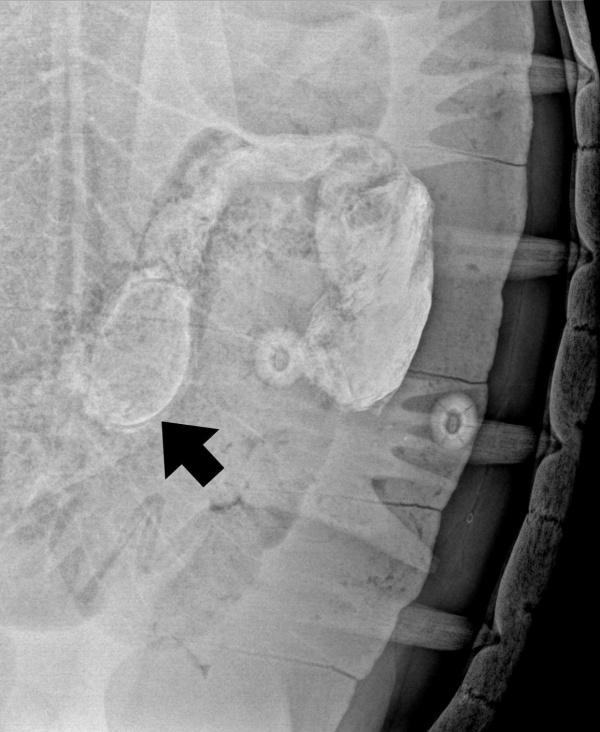

รายงานแจ้งว่า ทีมสัตวแพทย์ ได้ตรวจวินิจฉัยร่างกายเต่าอย่างต่อเนื่องตั้งแต่วันที่เกิดเหตุการณ์ ฉายX-ray ร่วมกับการกลืนสารทึบรังสี (Barium) พบสายรัดข้อมืออยู่ในทางเดินอาหารขนาดเส้นรอบวงประมาณ 20 ซม.ปะปนอยู่ในอุจจาระ ไม่อุดตันทางเดินอาหาร ตั้งแต่วันที่ 1 ธันวาคม 2568 การตรวจค่าเลือดอยู่ในเกณฑ์ปกติ กินอาหาร ขับถ่ายได้ปกติ การตรวจลักษณะของอุจจาระ พบเศษพืชและผลไม้ซึ่งไม่ใช่อาหารในธรรมชาติ ได้แก่ ใบสัปปะรด เม็ดมะละกอ และใบตองซึ่งย่อยไม่ได้ในทางเดินอาหารของเต่า

จากการประเมินสุขภาพต่อเนื่องทุกวัน ในวันที่ 18 ธันวาคม 2568 พบเต่าทะเลขับถ่ายโดยสายรัดข้อมือสีเหลืองและใบตองซึ่งย่อยเองไม่ได้ในระบบทางเดินอาหาร รวมเวลาตั้งแต่วันที่กลืนสายรัดข้อมือจนขับออกมา 27 วัน สัตวแพทย์ได้ประสานงานกับเจ้าหน้าที่อุทยานฯ วางแผนปล่อยเต่าคืนสู่ธรรมชาติในลำดับต่อไป โดยแนะแนวทางการจัดการกิจกรรมการท่องเที่ยวทางน้ำให้เหมาะสม ไม่ควรให้อาหารที่ไม่ได้เกิดขึ้นตามธรรมชาติและสิ่งแปลกปลอมให้กับเต่าทะเล